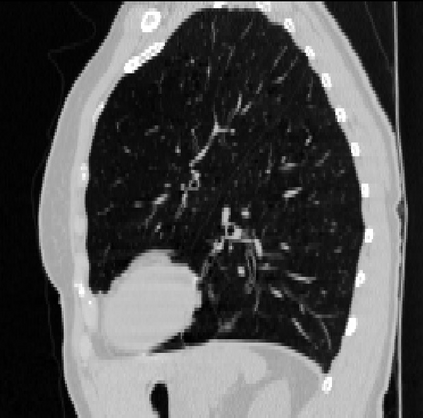

Deformable image registration is a fundamental task in medical image analysis and plays a crucial role in a wide range of clinical applications. Recently, deep learning-based approaches have been widely studied for deformable medical image registration and achieved promising results. However, existing deep learning image registration techniques do not theoretically guarantee topology-preserving transformations. This is a key property to preserve anatomical structures and achieve plausible transformations that can be used in real clinical settings. We propose a novel framework for deformable image registration. Firstly, we introduce a novel regulariser based on conformal-invariant properties in a nonlinear elasticity setting. Our regulariser enforces the deformation field to be smooth, invertible and orientation-preserving. More importantly, we strictly guarantee topology preservation yielding to a clinical meaningful registration. Secondly, we boost the performance of our regulariser through coordinate MLPs, where one can view the to-be-registered images as continuously differentiable entities. We demonstrate, through numerical and visual experiments, that our framework is able to outperform current techniques for image registration.